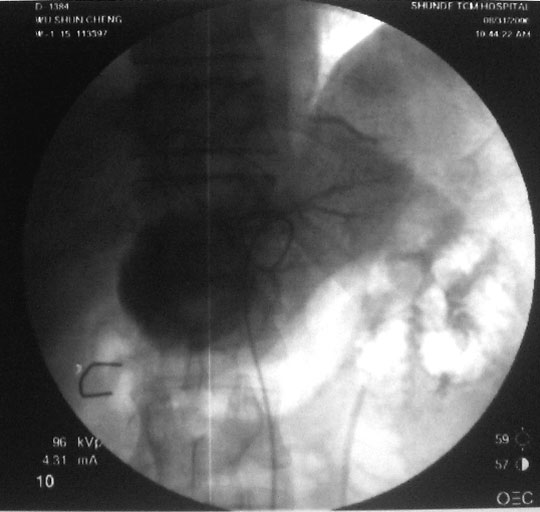

介入治疗过程:右股动脉穿刺,引入导丝导管,超选入肝固有动脉,造影显示肝右动脉肿瘤供血,圆球样肿瘤边界清楚。采用同轴导管进一步超选入右肝动脉、肿瘤血管边缘,注入化疗药+碘油混合剂7ml。

图1-3:导管进入肿瘤血管后造影,分别显示造影早期、中期、末期肿瘤情况。

图4:栓塞治疗后,肿瘤已为化疗药+碘油混合剂充填。